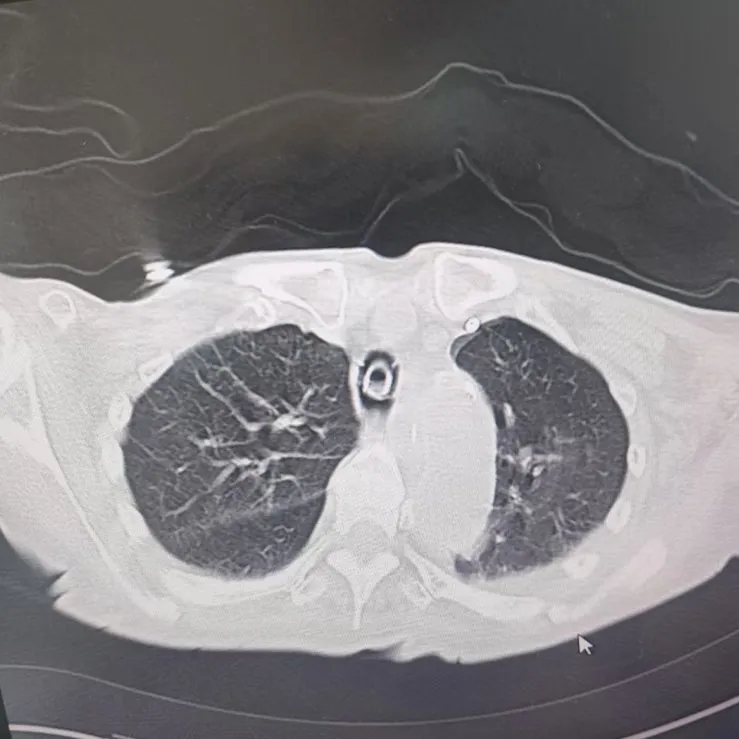

引言 / / Introduction 年近8旬的陈阿姨(化名)因脑梗长期瘫痪在床,康复期间突然高烧不退,体温升至39℃,在抗感染过程中,她并发高渗性脱水,病情急剧恶化,被紧急送入ICU。此时,她已气管切开,依靠呼吸机维持呼吸,并伴有低蛋白血症、低钾高钠血症及房颤等多种危重情况,命悬一线! PART. 01 多重泛耐药菌叠加大量基础病 治疗陷入“死胡同” 呼吸与危重症医学科及ICU通力协作,稳住患者生命体征。治疗过程中,进一步的病原学检查结果令人心惊:陈阿姨的肺部遭遇多种“超级细菌”混合侵袭,包括铜绿假单胞菌、鲍曼不动杆菌、嗜麦芽窄食单胞菌、金黄色葡萄球菌、木糖氧化无色杆菌、粘质沙雷菌等高度耐药菌,堪称耐药菌“大本营”。这些细菌对常用抗生素几乎全部耐药,治疗难度高,死亡率高。 治疗前患者肺部影像 PART. 02 多学科强强联手 量身定制攻坚方案 面对无药可用的困境,呼吸科没有放弃!宋刚主任带领团队联合药学部、检验科、重症医学科成立多学科治疗组,根据患者身体情况实时调整用药,逐一攻破耐药菌。这场与“超级细菌”的拉锯战持续了30多个日夜。 在医护日夜坚守和家属全力配合下,陈阿姨的感染终于被遏制:高烧退了,肺部阴影消散了!就在即将宣告胜利时,又发现她存在泌尿感染问题,随即转入泌尿外科协同治疗。当宋主任回访时,看到陈阿姨精神焕发、体温平稳,所有参与救治的人都感慨万分!这场救治,正是呼吸与危重症医学科攻坚耐药菌硬实力的生动体现! 治疗后患者肺部影像 从“无药可用”到“绝处逢生”,此次成功救治,集中体现了呼吸与危重症医学科以耐药菌精准诊治为核心的学科特色与技术优势。面对一次次的严峻挑战,科室始终秉持“生命至上、知难而进”的信念,以多学科协作为平台,凭借个体化精准用药策略,为患者寻找生机,为更多陷入困境的患者和家庭带去了实实在在的希望。 PART. 03 人民医院 人民名医 宋刚 主任医师 ·葫芦岛市第二人民医院呼吸与危重症医学科主任 ·辽宁省生命科学学会东北呼吸与危重症医学(PCCM)分会辽宁省基层委员会副主任委员 ·辽宁省细胞生物学学会放射粒子治疗专业委员会理事 ·辽宁省抗击新冠肺炎疫情先进个人 ·葫芦岛市劳动鉴定委员会专家库成员 ·葫芦岛市医学会呼吸内科学分会第三届委员会副主任委员 专业特色:擅长呼吸系统疑难及急危重患者的救治,如急慢性支气管炎、支气管哮喘、慢性阻塞性肺疾病、肺炎、肺栓塞、肺癌、间质性肺疾病、睡眠呼吸暂停综合征等,尤其擅长有创无创机械通气、支气管镜下相关检查及治疗(TBNA、气道支架置入术、球囊扩张等)、全肺灌洗术等领先技术,发表国家级期刊多篇。